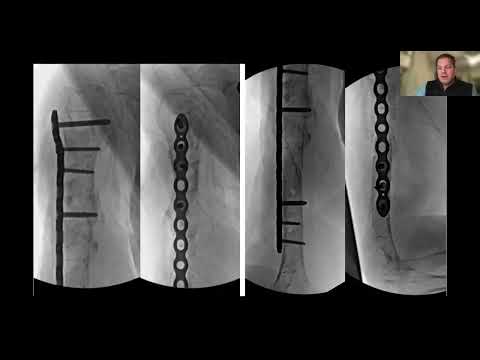

IlluminOss allows you to put screws where you want them, giving you stability, strength, and flexibility in your difficult cases. 🦴 #IlluminOss #Spreadthelight #Orthopedics

Pelvis is an approved indication in the US. For more detailed procedural information including Indications, Warnings, Cautions, Risks & Contraindications, visit illuminoss.com.